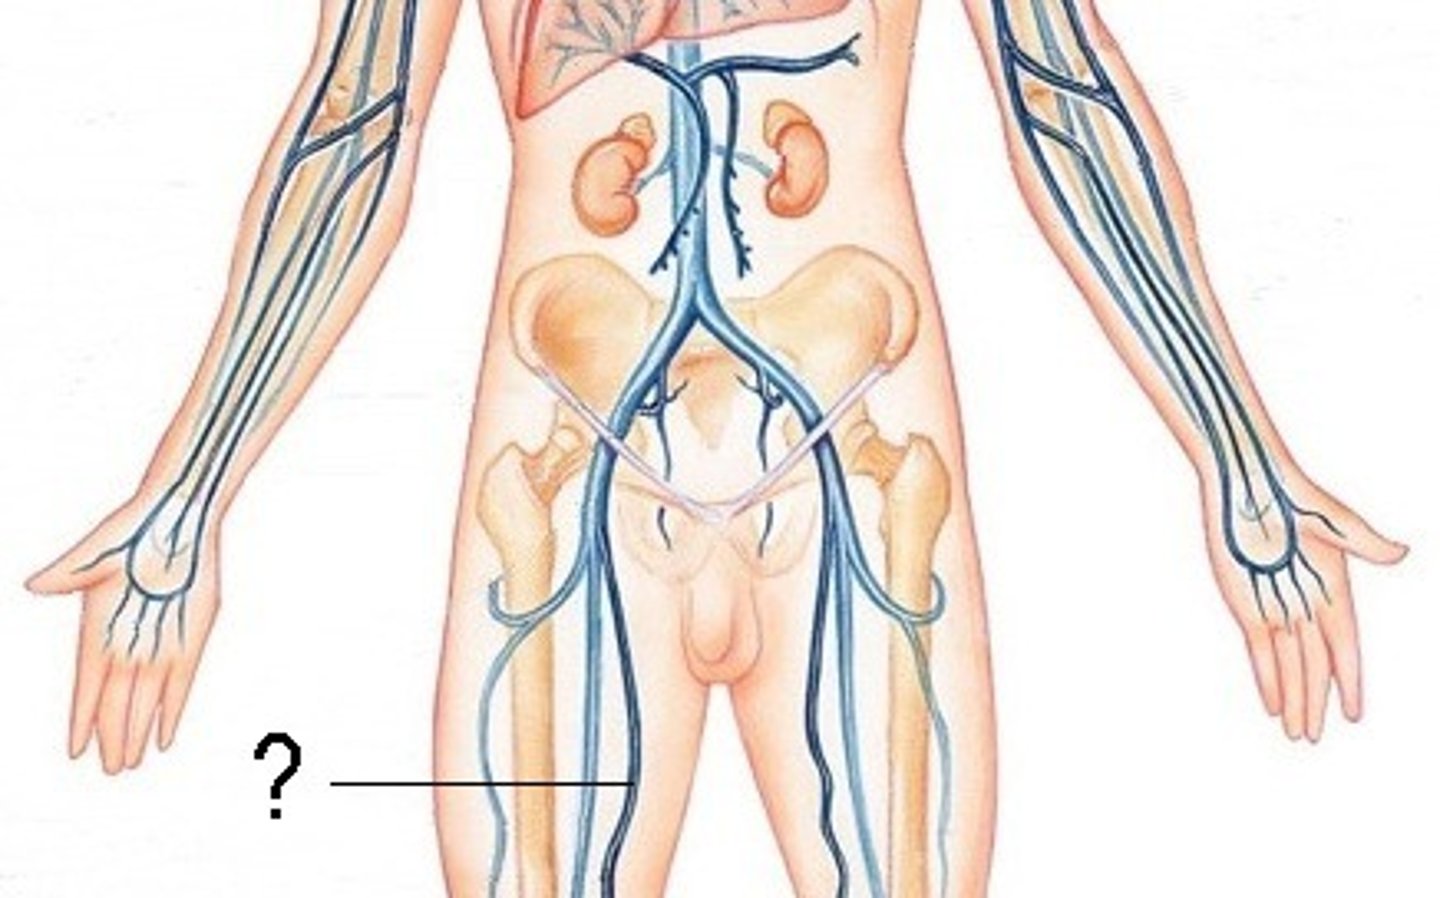

inferior vena cava

renal veins

left gonadal vein

right gonadal vein

common iliac vein

femoral vein

saphenous vein

longest vein in the body

popliteal vein

anterior tibial vein

posterior tibial vein